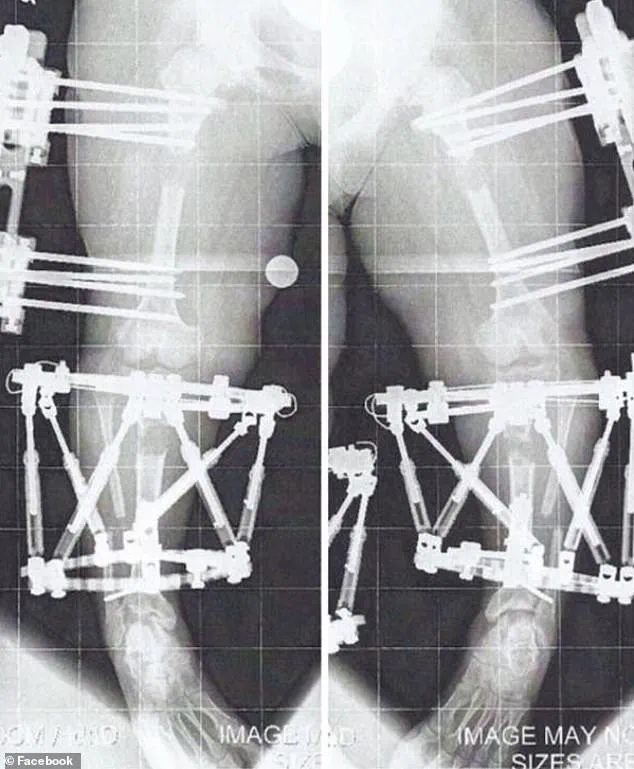

Limb-lengthening surgery, which involves surgically cutting bones and using external or internal devices to gradually stretch them over weeks or months, is a painful, expensive, and risky process.

In August 2010, at the age of 16, Crews underwent her first of three limb-lengthening procedures, a decision that marked a turning point in her life.

Her journey, which included three separate surgeries, ultimately increased her height from 3'10'' to just over 4'11''.

Limb lengthening surgery, a complex and often grueling medical procedure, involves the deliberate breaking of bones to allow for gradual extension and new bone formation.

The process, known as the 'distraction phase,' requires the bones to be extended by approximately 1 millimeter per day.

This slow, methodical approach allows the body to generate new bone tissue in the gap created by the surgical intervention.

Once the desired length is achieved, the external or internal fixators used during the procedure are removed.

Crews, who underwent three limb-lengthening procedures, described the experience as 'months of twists and turns' filled with 'a little blood, sweat, and tears.' Her first surgery took place in August 2010, and the process involved surgically cutting the bone and implanting a device—either an external fixator or an internal rod—to facilitate the gradual lengthening.

The recovery from her first surgery was arduous, requiring two to three hours of personal training sessions five days a week, along with daily exercises and stretches performed independently.

By April 2011, the fixators were removed from her first leg, but she had to endure a month of non-weight-bearing before she could begin the process of relearning how to walk.

This involved using a walker, then quad canes, and eventually walking unassisted by June of that year.

For her arm lengthening procedure, fixators were implanted in January 2012 when she was 17 years old and removed the following August.

Unlike the leg surgeries, this procedure allowed her to remain mobile, as the fixators were placed on the humerus, the bone of the upper arm, rather than on the lower limbs.

The medical process of limb lengthening is complex, involving the deliberate breaking of bones and the use of external or internal fixators to gradually stretch the tissue.

According to medical professionals, weight-bearing activities are often critical to accelerating the consolidation phase, where bones heal and fuse.

However, Crews notes that the absence of weight-bearing in her arms—due to the nature of the procedure—slowed this process. "After removing my fixators, I had about a month of no heavy lifting, pushing, or pulling," she recalls.